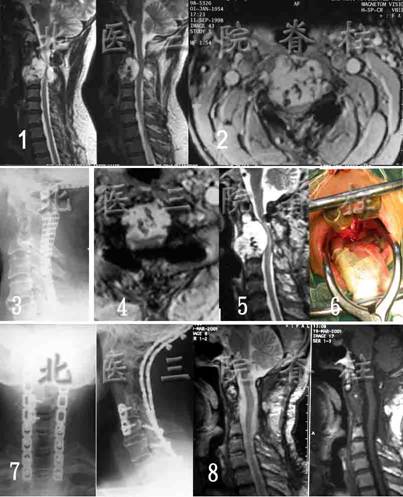

上颈椎肿瘤全椎切除(前路经口入路)重建手术

患者,男性,49岁。因颈后部疼痛5年,于在外院发现C2-5肿瘤。行后路肿瘤切除,C2-3椎板切除减压钛网内固定术,病理示脊索瘤。术后症状短暂缓解后很快加重,伴四肢不全瘫。转入我院。

术前Halo-vest固定,全麻下前后联合C2,C3,C4(全椎切除)及C5(部分椎体)切除软组织内肿瘤切除,枕颈钢板内固定,齿突-C5椎体间植骨术,其中前路手术采用经口入路。病理为脊索瘤。术后四肢症状消失。恢复正常工作。